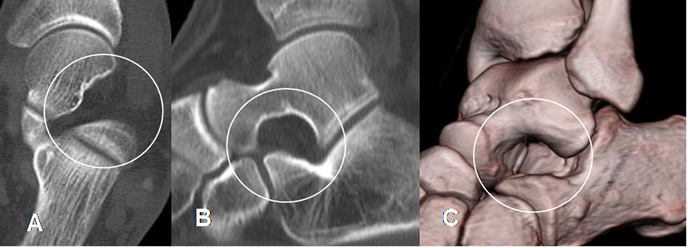

Fig 106. Seno del tarso normal.

A: TAC axial, B: TAC reconstrucción sagital y C: TAC en reconstrucción 3 D.

Espacio normal en la parte lateral.